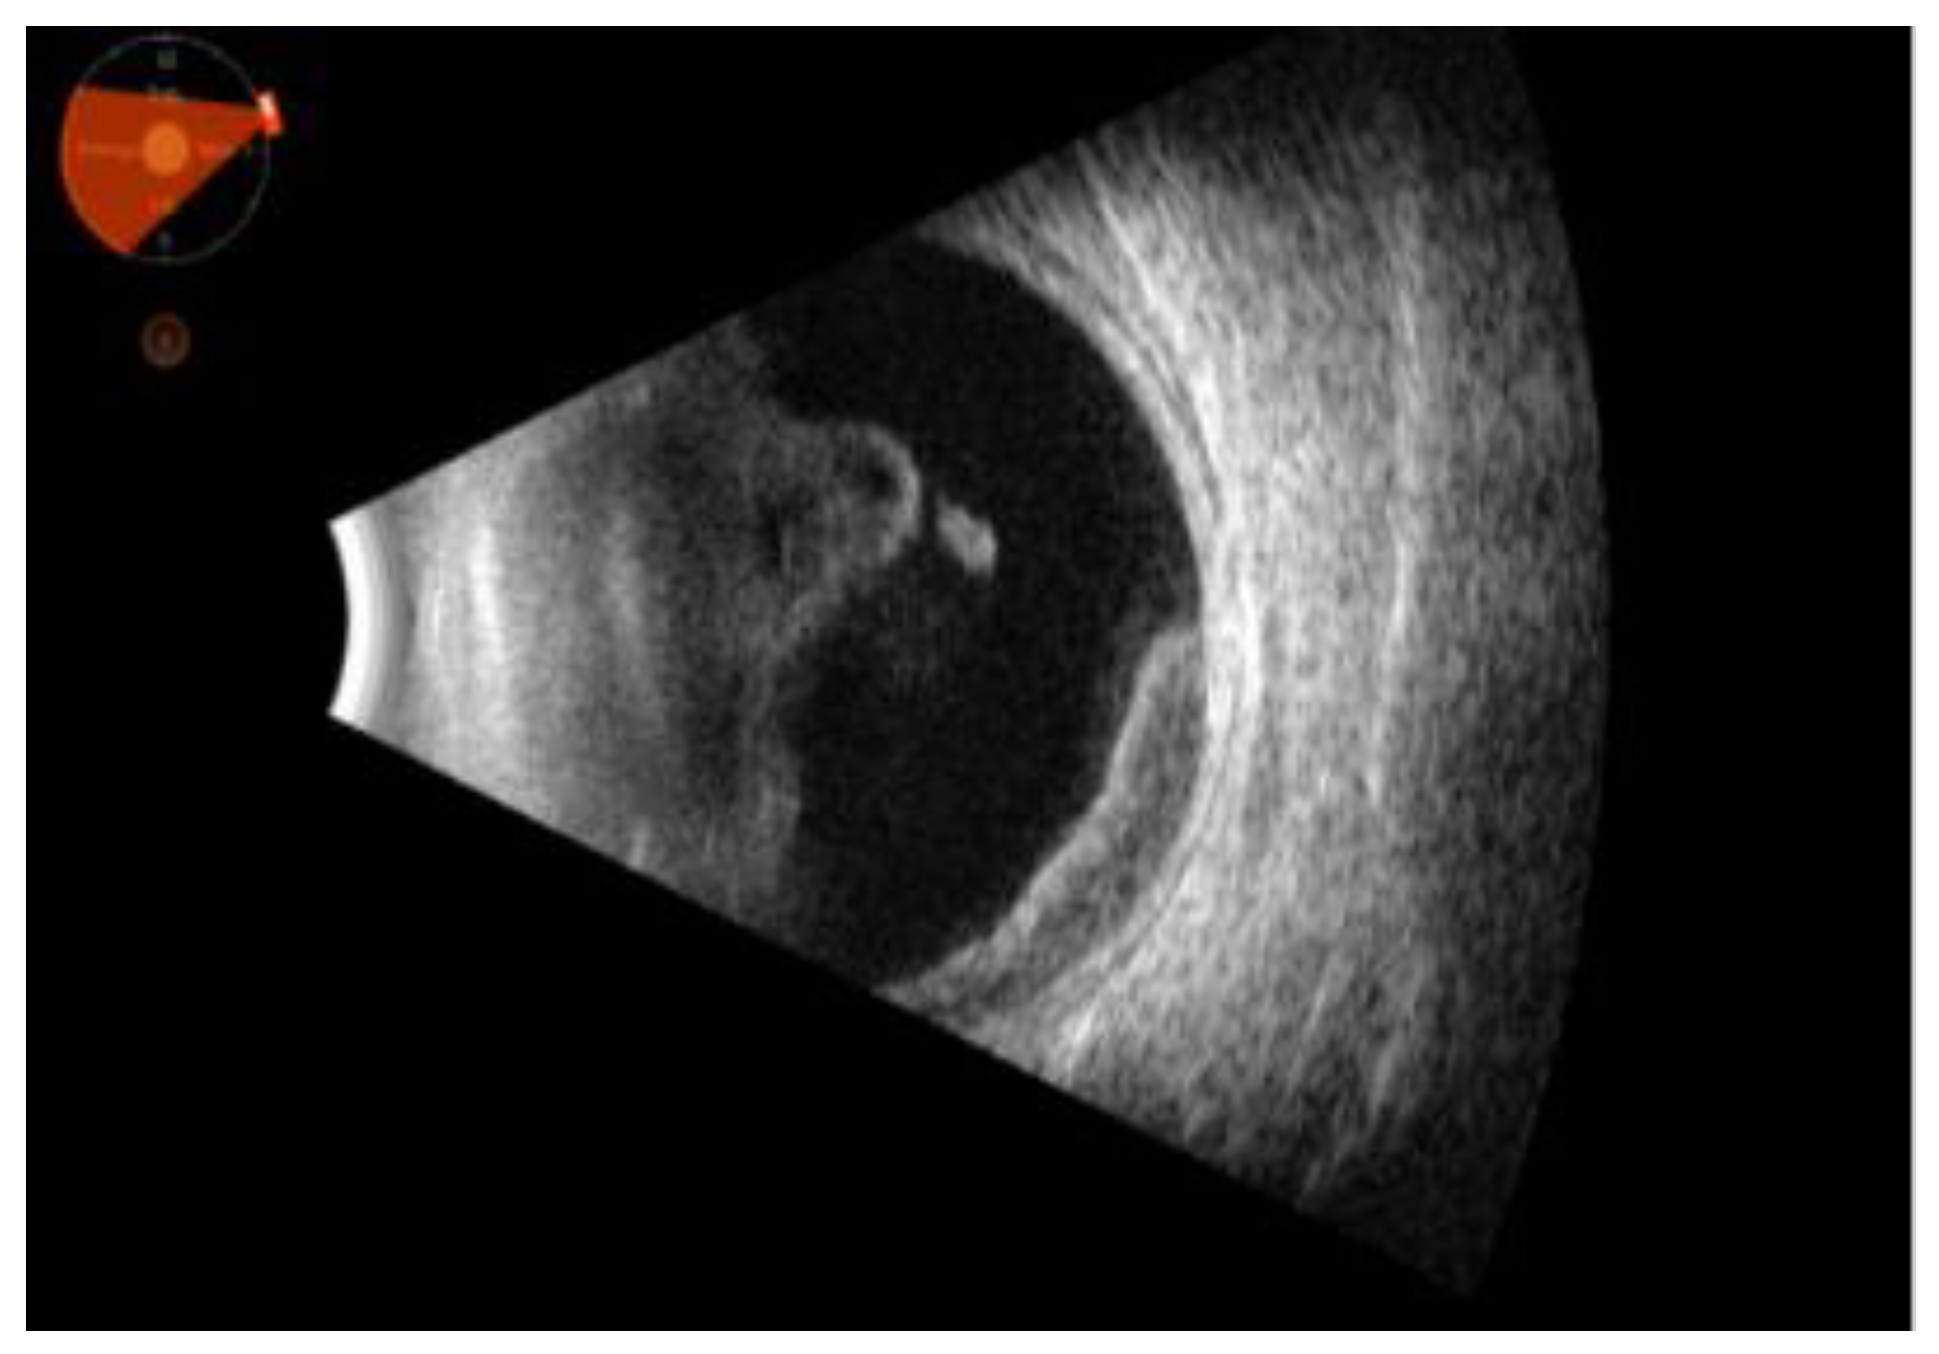

Figure 2. describes an ultrasound picture of abundant vitreous corpuscles organized in clusters in the anterior vitreous, high cellularity and mobility. Moreover, the following is appreciated a highly cellular structure with medium-high reflectivity in the temporal sector, at times in continuity with the vitreous (intraocular lymphoma).